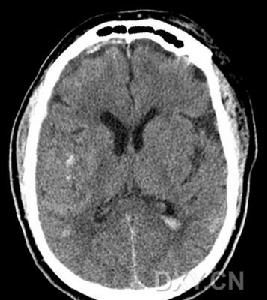

4、颅脑CT可见脑内大小不等、边界不清的低密度灶。

5、放射学检查:常规头颅放射学检查对散发性脑炎的诊断无重要价值。头颅CT有时可见大脑半球多个散在的软化灶,对排除占位性病变有一定意义。 医学百科网 | YxBaike.Com